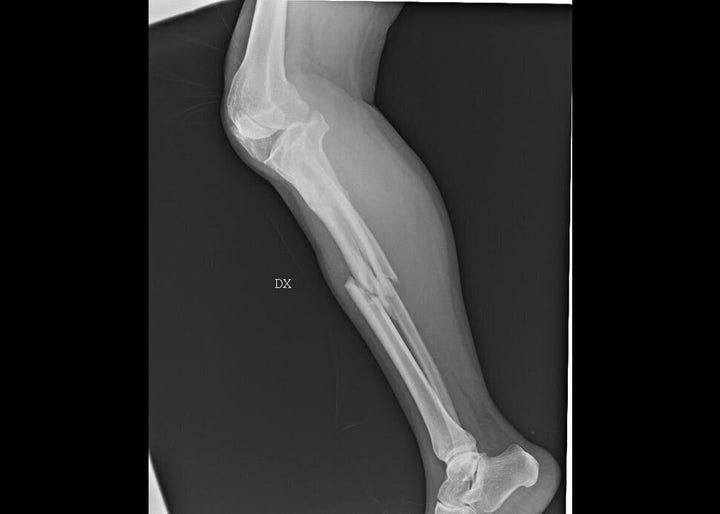

This isn’t the beginning of a novel, but the true story of a woman featured in “Invisibility Is Not A Superpower,” an exhibition that was set up in the atrium of the San Carlo Hospital in Milan, Italy, from Nov. 21 to Dec. 8. Through anonymous photographs and X-rays, the exhibition recounts the tragedy of women arriving at the emergency room and reporting that they have been victims of domestic violence.

“In this exhibition, a voice is given to the bodies and injuries of women who have suffered violence, weaving individual stories into a single narrative,” said photographer Marzia Bianchi. “The lives of the women differ, yet the pattern of violence is repeated, mainly at the hands of a partner, relative or acquaintance.”